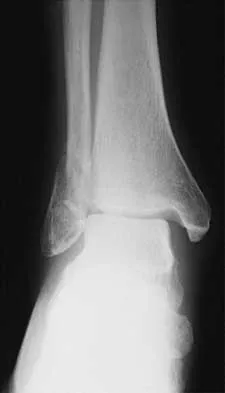

A 57-year-old man has had right ankle pain for the past 10 months following an injury that went untreated. Radiographs are shown in Figures 30a through 30c. Management should consist of